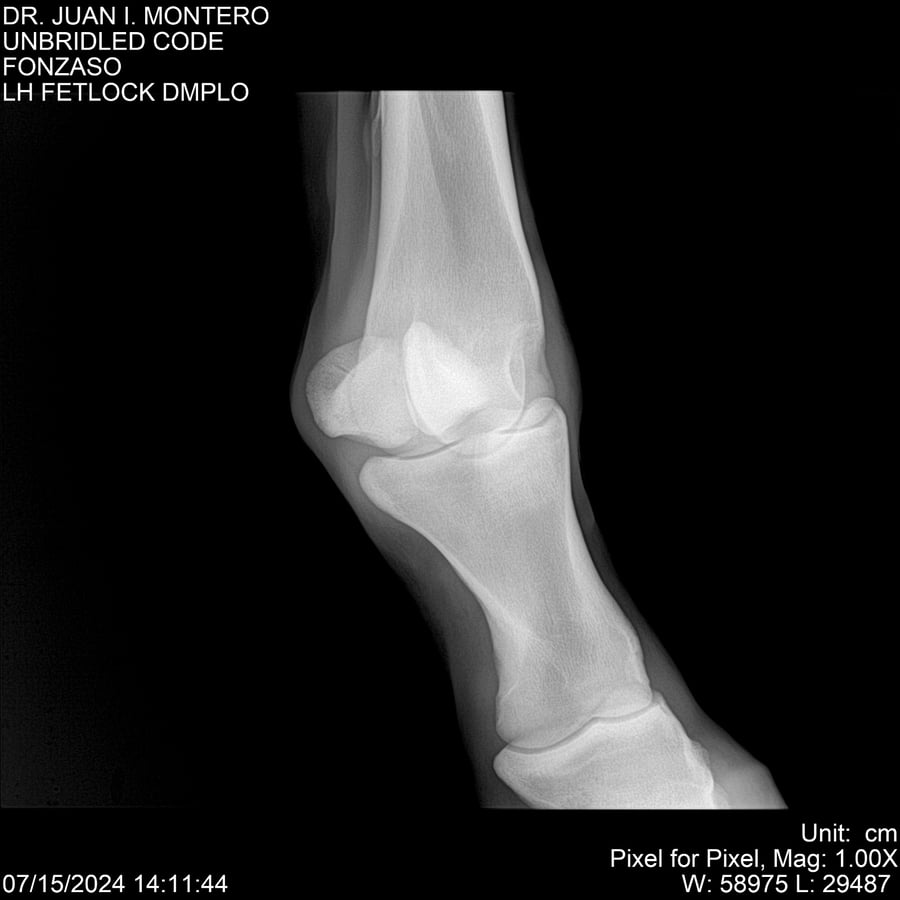

• Empresa: Abelenda N. R., Walter Hugo